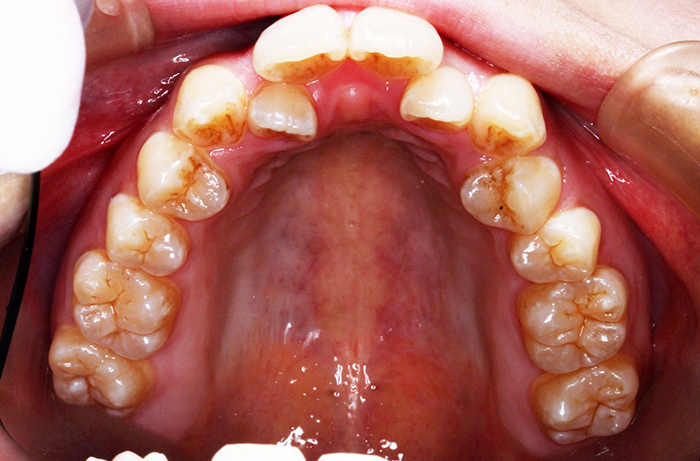

A様

治療前

before

年齢 31歳

性別 女性

治療名称 マウスピース型カスタムメイド矯正歯科装置(インビザライン)・コンプリヘンシブパッケージ(難症例)

総額治療費用 935,000円(税込10%) 金額備考 精密検査料・診断料 33,000円(税込10%)

治療期間 3年4か月 通院頻度など 1か月ごと(途中から3~4か月ごと)

患者の症状 叢生、正中のずれ、上顎左右側切歯の口蓋側転位(交叉咬合)

治療方法 非抜歯で、マウスピース型カスタムメイド矯正歯科装置(インビザライン)による矯正

歯列弓を拡大することで非抜歯を可能にしました。

治療結果 側切歯の交叉咬合は解消、上下正中のずれも改善し咬み合わせが良くなりました。